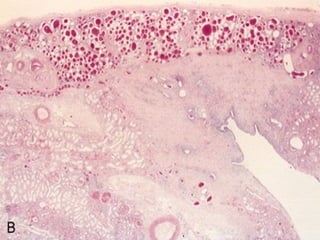

Analgesic nephropathy

 Morphology:

 Papillary necrosis is the characteristic

finding.

 The papillae appear yellowish brown due

to accumulation of drug products.

 Microscopically

The papilla show: Coagulative necrosis

 With loss of cellular details and

 Preservation of tubular outline.